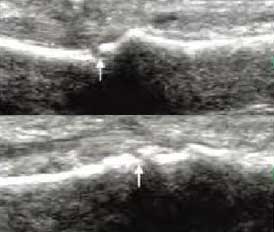

4、具备软组织超高分辨率 区分关节受损层级

肌骨超声通过平面成像能力发现RA关节软骨微小病变,早期就能准确反映出软骨下骨质线回声增高程度,关节软骨表面是否毛糙模糊凹凸不平、形态是否规则、有无明显隆起或缺损形成,判断早期RA软组织改变及RA骨质受损状况。

超声对软骨改变、骨质侵蚀 评分

• Ⅰ级

骨表面欠平整

骨关节面边缘不整齐、模糊,形成不规则间隙

• Ⅱ级

骨质中断或缺失

骨表面出现弧形条状低回声,软骨表面不规则变薄、缺损形成

• Ⅲ级

骨表面凹凸不平

骨表面缺损融合成广泛的骨质破坏、侵蚀